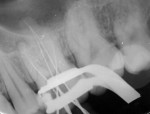

A 25-year-old male patient reported to the outpatient department with the chief complaint of pain in the left upper back region of jaw for the last 2 to 3 days. The patient also gave a history of disturbed sleep. Findings from the clinical examination revealed a deep carious lesion in the maxillary left first molar. The tooth was sensitive to percussion and elicited positive response on thermal and electric pulp testing; pain persisted even after removal of the stimulus. An intraoral periapical radiograph revealed a radiolucency approximating the pulp and periodontal ligament space widening was also present (Figure 1). On correlating the clinical and radiographic findings, a diagnosis of acute irreversible pulpitis with apical periodontitis was made and a decision to perform root canal treatment of maxillary left first molar was determined. The patient was informed about the treatment, and he provided informed consent. The patient was administered local anesthesia of 2% lidocaine containing 1:80,000 epinephrine and an access opening was performed using a rubber dam isolation. The clinical evaluation of the internal anatomy revealed 3 principal root canal systems: mesiobuccal (MB), distobuccal (DB), and palatal (P). After careful probing using a DG 16 endodontic explorer (Dentsply Sirona, dentsply.com), under 2.5X magnification using surgical loupes (Keeler Instruments, keelerusa.com), a small hemorrhagic point was noticed in a groove from the MB orifice in a palatal direction. A similar hemorrhagic point was also observed near the orifice of the main palatal canal. The conventional triangular access was modified to a trapezoidal shape to improve access to the additional canals. In both areas, there was a “catch” present with the endodontic explorer. Multiple radiographs at different angulations were not conclusive, so a multislice CBCT (Kodak, Carestream, carestreamdental.com) scan was performed of the involved tooth along with adjacent teeth. All required measures were taken to protect the patient from radiation. The images were obtained in transverse, axial, and sagittal sections of 0.5-mm thickness, which is used routinely. CBCT scan slices revealed 5 canals (2 mesiobuccal, 2 palatal, and 1 distobuccal) in the axial images at the coronal (Figure 2) and middle thirds (Figure 3). In the apical third, the palatal root had only 1 canal indicating that the 2 canals were fused between middle and apical thirds (Figure 4).